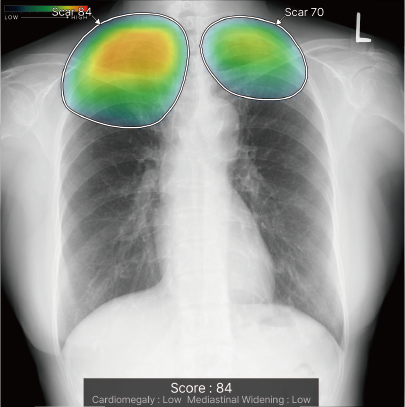

CXR-AIDが候補領域の解析をおこなったのち、0~100に応じた確信度を色分けして表示。

検出領域ごとに所見名を表示します。

対象所見のそれぞれの確信度の最大値が所見ごとに個別に表示されます。

ヒートマップと輪郭の表示は3パターンから選択可能です。